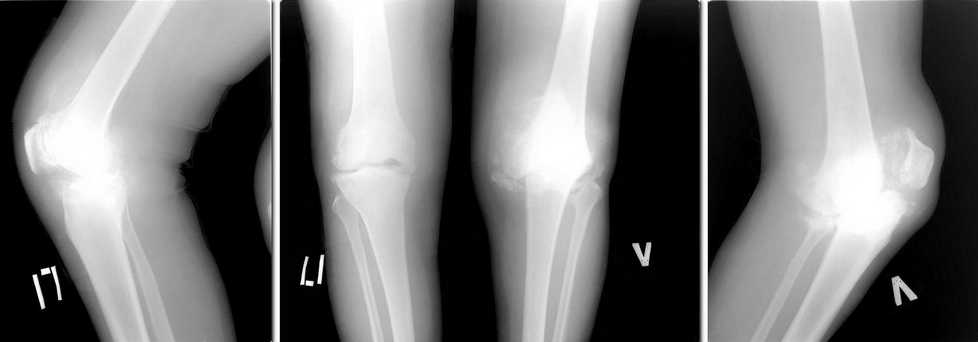

Здравствуйте коллеги, возможно кто-то сталкивался с подобной ситуацией. Пациента беспокоят боли в коленных суставах в течении 5 лет.

1,5 года назад установлен диагноз: Нейросифилис. Находится на диспансерном наблюдении у венеролога. Обследован онкологом, фтизиатром - "своей" патологии не находят. Бакпосев синовиальной жидкости - нет роста. Боли в коленях постоянные. Ходить может. Разгибание полное, сгибание 90*. На представленных рентгенограммах в сравнении с предыдущими, 2 месячной давности (в настоящее время не располагаю), добавился патологический перелом медиального мыщелка левого бедра. Природа артроза не ясна, однако, умозрительно - нейросифилис.

Дилемма такова: 1)Эндопротезирование? но беспокоит вопрос о стабильности компонентов протеза в будущем, а следовательно и целесообразности деяния. 2)Артродезирование? - состоится ли артродез на фоне продолжающегося разрушения костей. Обе операции технически вполне выполнимы. И последнее - следует ли оперировать. Заранее спасибо за добрые советы.

Сейчас снимок виден. Типичный Шарко.Артродез, конечно, технически много проще.

Charcot arthropathy is differrent from degenerative. Charcot knee should be inactive and than operated. Is it warm now?I would first immobilize for long and fuse. Look up for the criteria for Charcot.